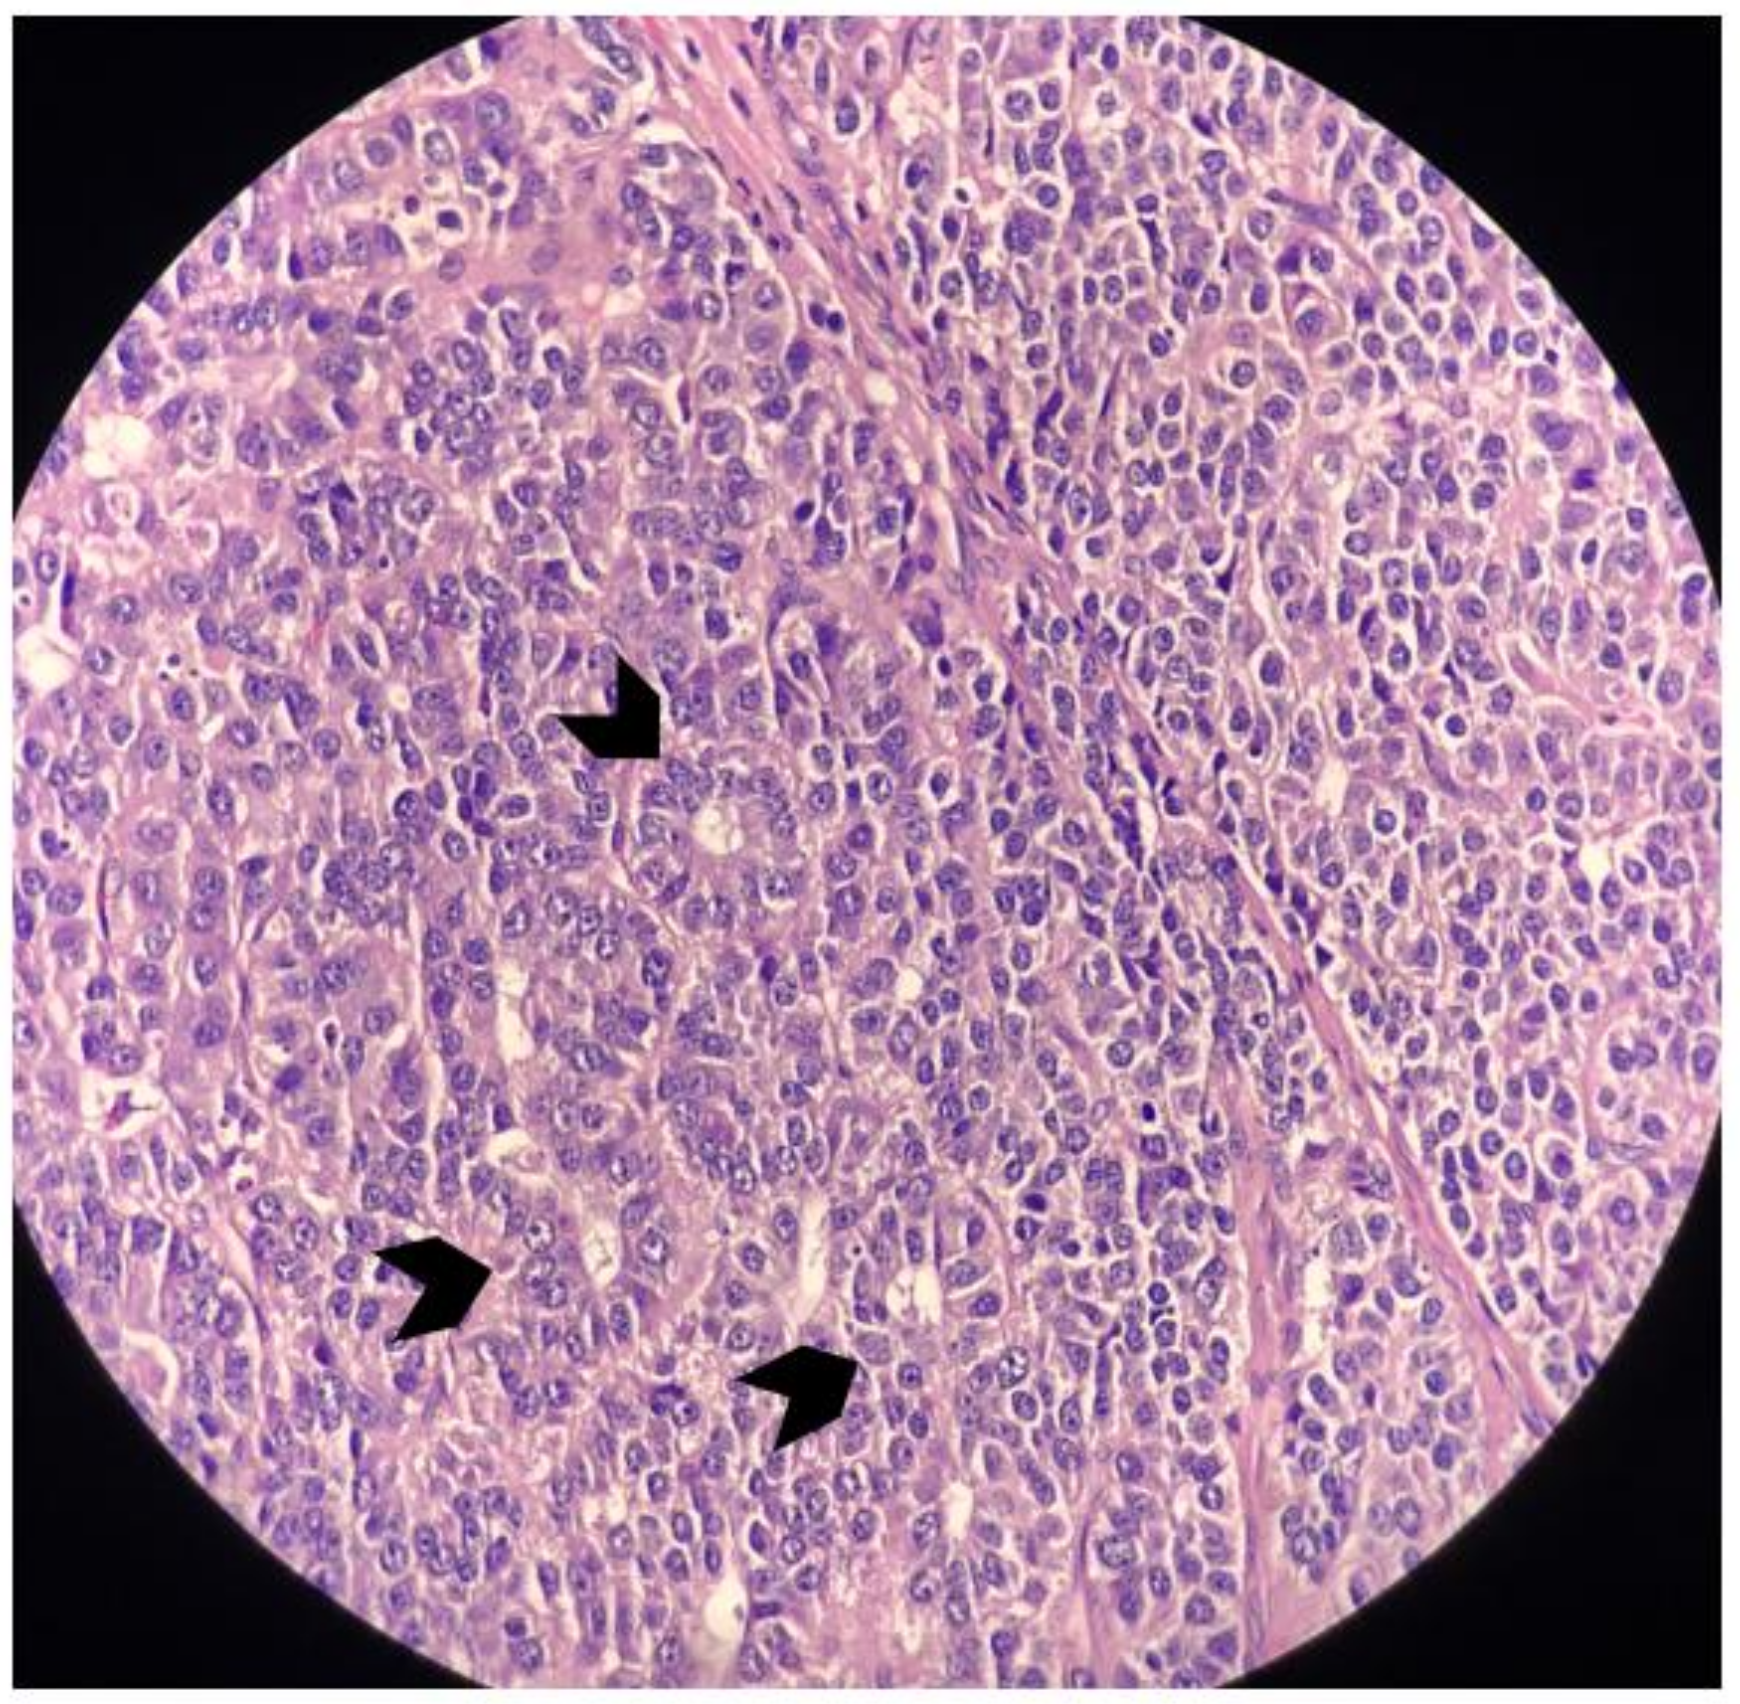

2. Case Report

3. Discussion and Literary Review